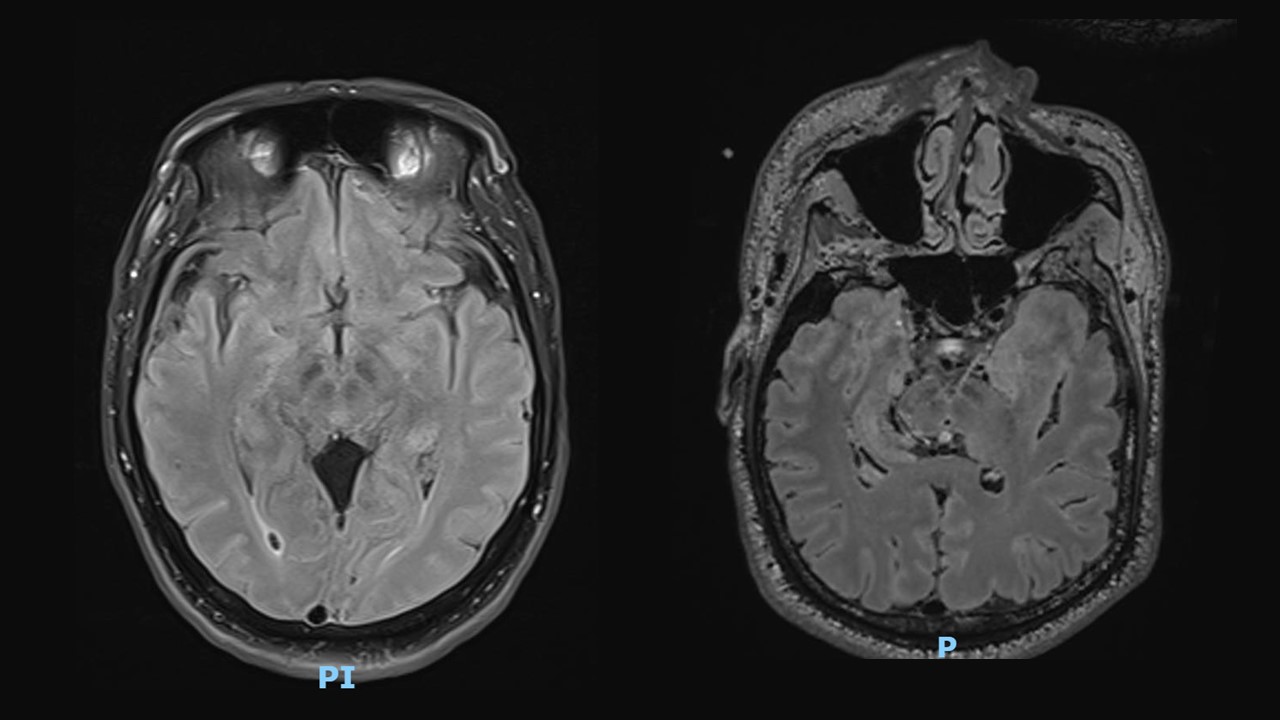

Figure 1. Atrophy of midbrain